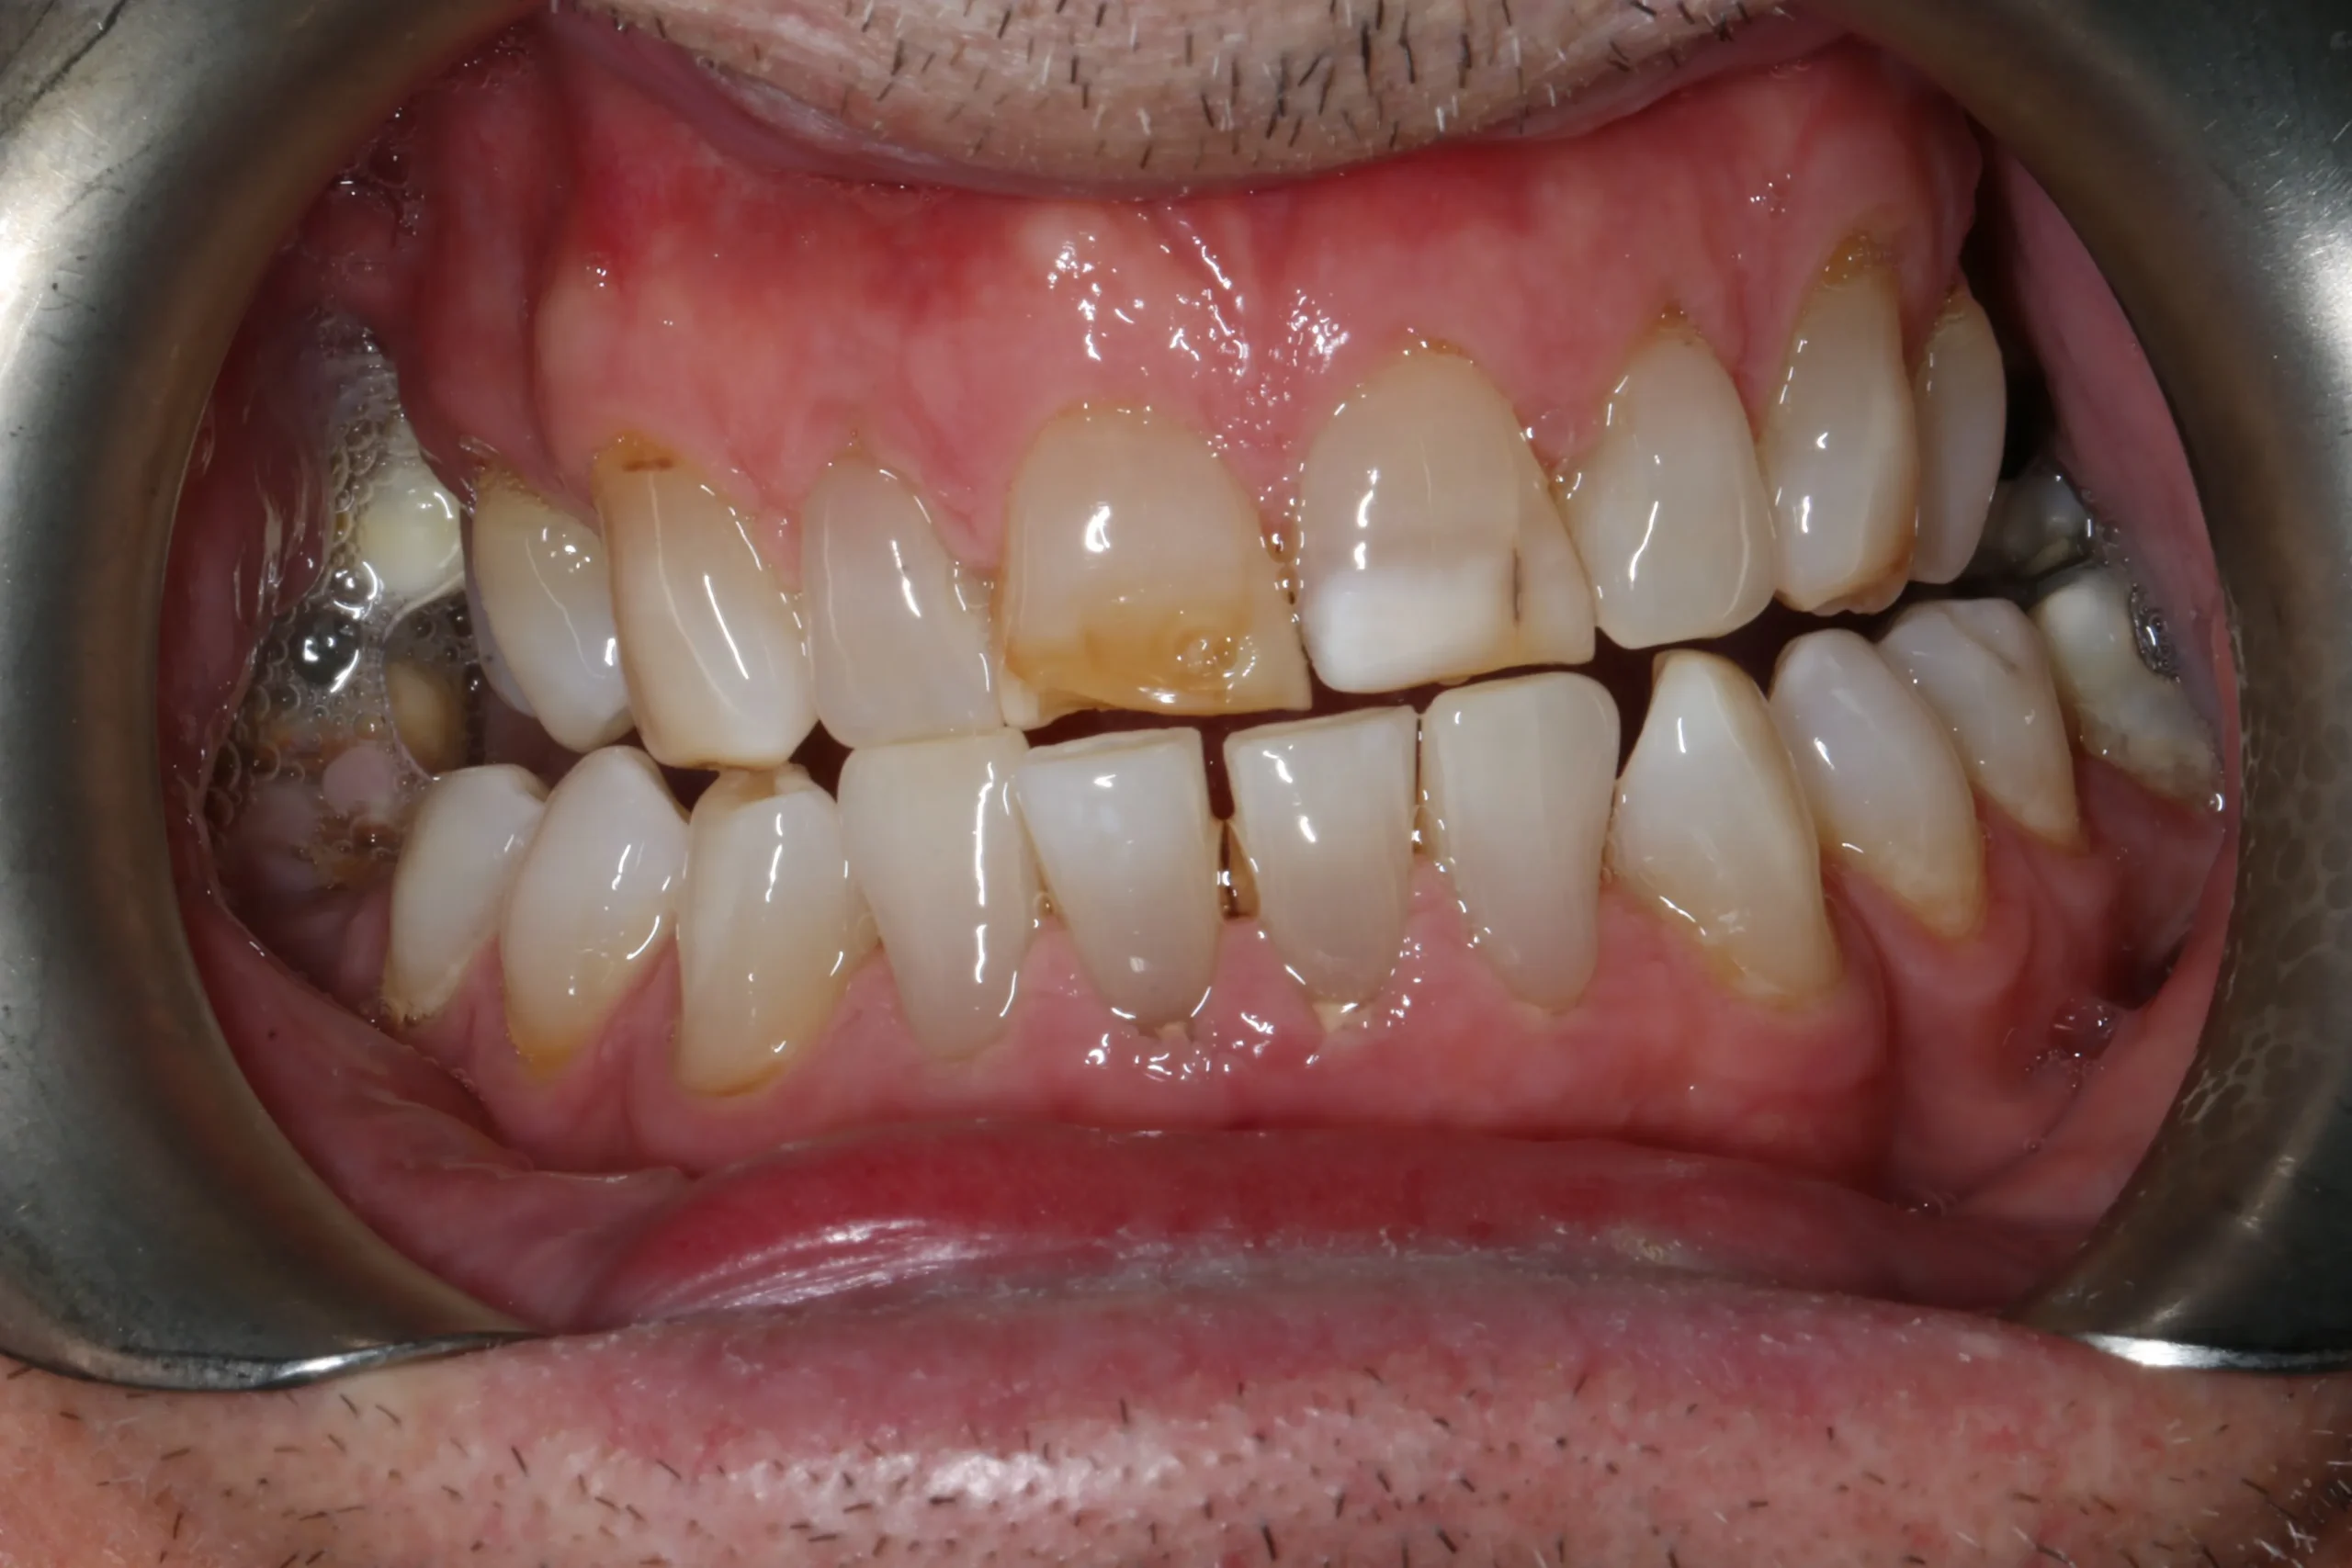

Worn, discoloured and chipped upper front teeth.

Before